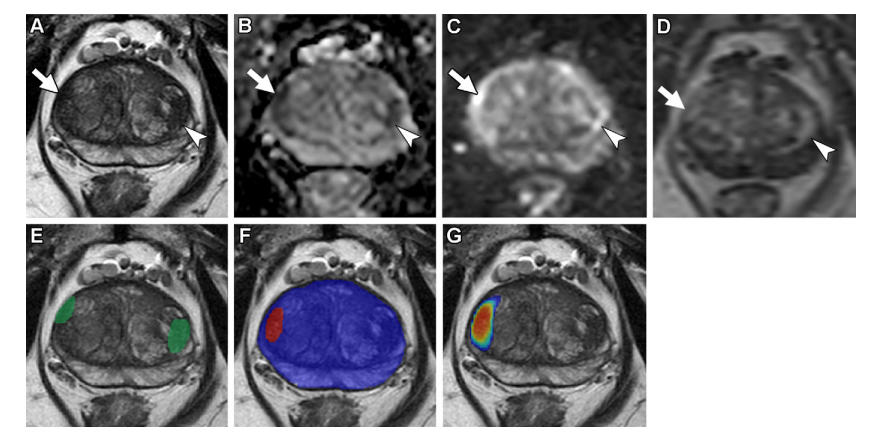

Figure 3 illustrates axial multiparametric MRI scans conducted on a 72-year-old male participant with elevated serum prostate-specific antigen levels (9.1 ng/mL). The imaging findings revealed several key findings: (A) a T2-weighted image demonstrating parenchymal density, (B) an apparent diffusion coefficient map highlighting areas of reduced water diffusion, (C) a high-b-value diffusion-weighted image emphasizing white matter tracts, (D) a dynamic contrast-enhanced image showing temporal variations in lesion enhancement patterns, (E) a T2-weighted image overlaid with radiologist-segmented lesions marked in green, (F) an AI prediction map overlaid on T2-weighted images with red contours indicating positive predictions and blue contours delineating AI-predicted prostate organ structures, and (G) an AI probability map overlaid on T2-weighted images using red to indicate regions with higher likelihood of malignancy. Two distinct lesions were identified by radiologists as the ground truth: Lesion 1 measuring 1.6 cm located in the right midgland transition zone was classified under PI-RADS category 4, while Lesion 2 measuring 1.5 cm positioned in the left midgland transition zone was categorized as PI-RADS category 3. While Lesion 1 was successfully identified as malignant through targeted biopsy analysis, Lesion 2 proved resistant to detection by the AI algorithm, classified as a false negative. Biopsy results confirmed that Lesion 1 exhibited Gleason score 7 (3 + 4) prostate adenocarcinoma characteristics, whereas Lesion 2 demonstrated benign characteristics without histological evidence of malignancy.

图3展示了72岁男性的轴向多参数轴向扩散加权MRI扫描结果:(A) T2加权回声图像;(B) 表观扩散系数映射图;(C) 高b值的空间分辨率(T2-1500 sec/mm²)回声图像;(D) 5.6秒动态对比增强序列第17帧;(E) 基于放射科医生分割病灶绿色轮廓的T2-1500 sec/mm²回声图像;(F) 基于AI预测区域红色轮廓及蓝色区域显示AI识别的前列腺器官分割结果;(G) 基于AI概率评估红色区域标记的概率分布图。放射科医生确认存在两个独立病灶:第一个位于右侧腺体过渡区大小约1.6厘米(Gleason 7/3 +4分型)被正确诊断为前列腺腺癌;第二个位于左侧腺体过渡区大小约1.5厘米被归类为PI-RADS 3类病变但未被正确诊断。通过活检样本确认病灶1为局部晚期前列腺腺癌而病灶2为良性肿瘤